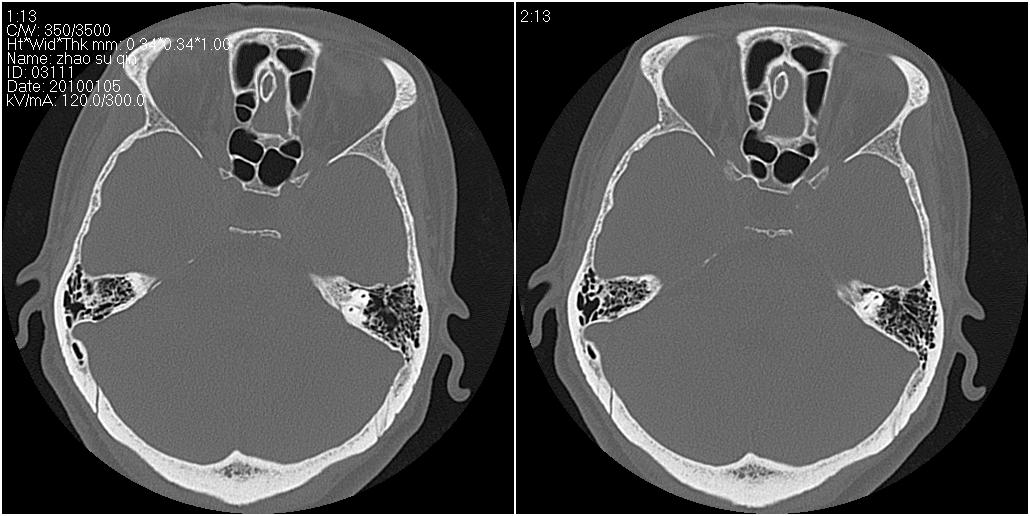

标题: CT24015:一个头部外伤患者进行鉴定,除了左侧筛板骨折,哪 [打印本页]

标题: CT24015:一个头部外伤患者进行鉴定,除了左侧筛板骨折,哪

左眶下裂部好像有骨折 似有小碎骨片

1)左侧筛板骨折。2)双侧筛窦炎症(或积血)。